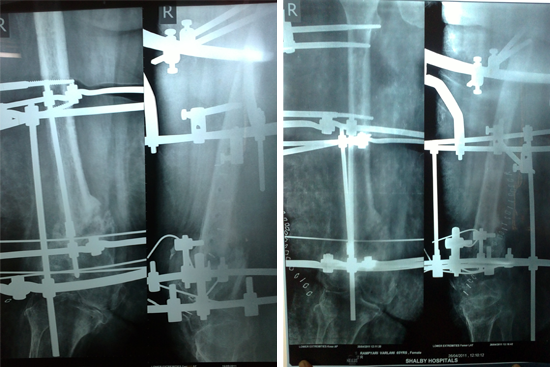

Non Union Femur

Case 1

Case 2 (Rampyari)